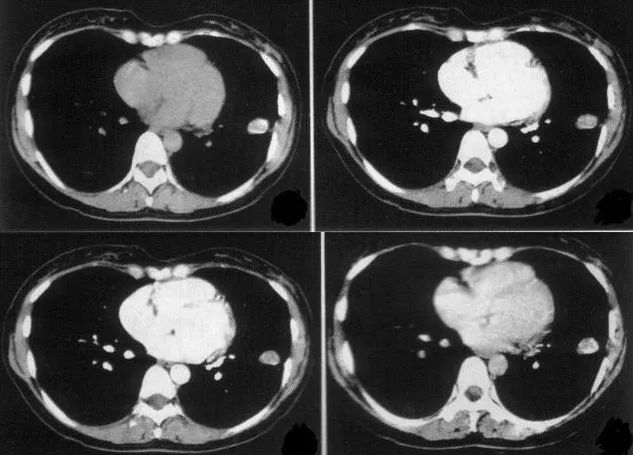

首先我们得明确,哪些肺结节应该观察,哪些肺结节应该及时地去干预。根据结节是恶性倾向的概率,也就是说恶性倾向概率越低,患者随诊的间歇越长,如果说暂时还不能判定结节的良恶性,只是怀疑,随访间歇会比较短。观察过程当中,如果这个结节增大,它是恶性概率可能就变高了,如果结节稳定不变,良性的概率就比较高。

所以往往我们第一次发现肺结节的时候,下一次复查时间会较短,医生可能会要求1-3个月就进行第一次复查。如果第二次复查之后,发现肺结节跟之前没有明显变化,可能就会把复查间歇拉长。